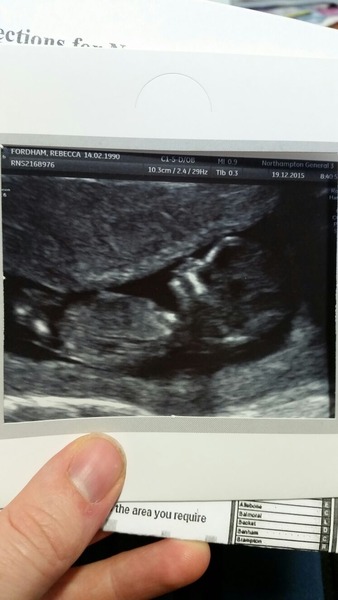

ifigoup · 20/12/2015 11:14

Does anyone want to speculate about the sex of this 13-weeker? If what I think is the nub is in fact the nub then it looks flattish, but I'm not sure I'm even looking at the right bit!

Ifigoup upload your pic on ingender they are really clued up on the theories like skull and nubs. I'm not sure the pic shows it or not but they will tell you